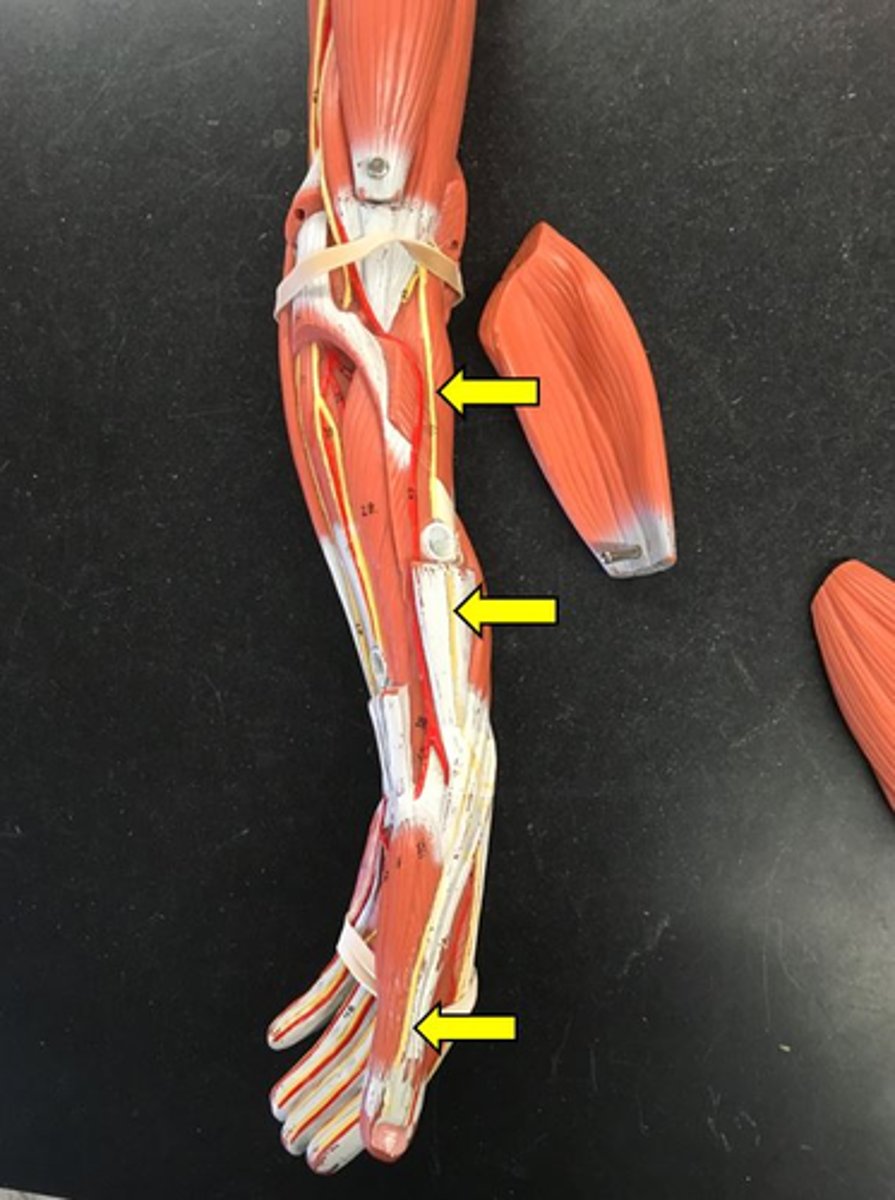

musculocutaneous nerve

median nerve

ulnar nerve

radial nerve

saphenous nerve

common fibular nerve

tibial nerve